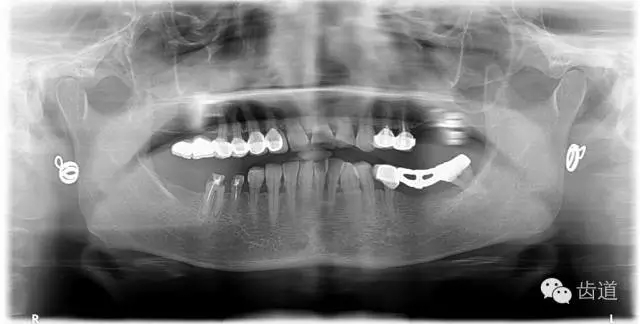

1、術(shù)前全景片

2、45,46術(shù)前片顯示根管上段充填物,根管影像不清晰,少許根尖暗影

3、34術(shù)前片顯示遠(yuǎn)中面暗影近髓